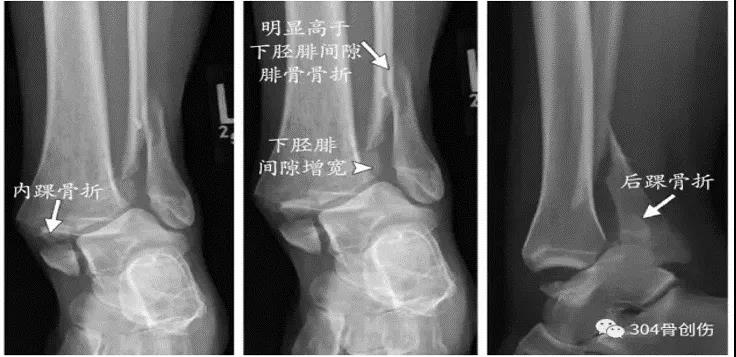

Lauge-Hansen-旋后内收(SA)足呈跖屈内收内翻位,内翻的距骨使踝关节外侧韧带紧张。Ⅰ°:外踝撕脱性骨折或外侧韧带损伤。Ⅱ°:外力继续作用,内踝受到内翻的距骨的挤压作用,造成内踝骨折。(特点:内踝骨折线倾向垂直)

Lauge-Hansen-旋后外旋(SE)损伤时足呈跖屈内收内翻位,距骨外旋(胫骨内旋)。Ⅰ°:距骨外旋使腓骨受到向外、向后的应力,下胫腓前韧带损伤或韧带附着点撕脱性骨折,或者同时又骨间韧带损伤。Ⅱ°:外力继续作用,腓骨继续受到向外、向后的旋转应力,造成腓骨的螺旋性骨折。(特点:腓骨骨折线从后上向前下。并且多位于下胫腓联合部位。)Ⅲ°:外力继续作用,下胫腓联合后韧带紧张,造成下联合后韧带的断裂或后踝的撕脱骨折。Ⅳ:外力还继续,距骨旋转使三角韧带紧张,造成内踝的撕脱性骨折或者是三角韧带的断裂

Lauge-Hansen-旋前外旋(PE)受伤时,足处于旋前背伸外展位,距骨外旋。Ⅰ:三角韧带紧张,造成三角韧带损伤或者是内踝撕脱性骨折。Ⅱ°:外力继续作用,距骨外旋造成下胫腓前韧带和骨间韧带损伤,或者韧带附着点撕脱性骨折。Ⅲ°:外力继续作用,腓骨受到向外向后的旋转应力,造成腓骨的螺旋性骨折(特点:腓骨由于足本身的位置,外旋力大,向上传导,骨折位于下联合上方,甚至可以达到腓骨颈部位- Maisonneuve骨折)。Ⅳ:外力继续作用,下胫腓后韧带紧张,造成下胫腓后韧带断裂或后踝撕脱骨折。

Lauge-Hansen-旋前外展受伤时足处于旋前位,距骨外展,三角韧带紧张Ⅰ:内踝撕脱性骨折或三角韧带损伤。Ⅱ:外力继续,外展的距骨造成下联合前后韧带同时紧张,断裂,或者韧带的撕脱性骨折,骨间韧带和骨间膜的撕裂。Ⅲ:外力继续作用,距骨挤压腓骨,造成腓骨的短斜形骨折(特点:外侧有一蝶形小碎骨片,骨折线多位于下联合上或者在下联合部位)。